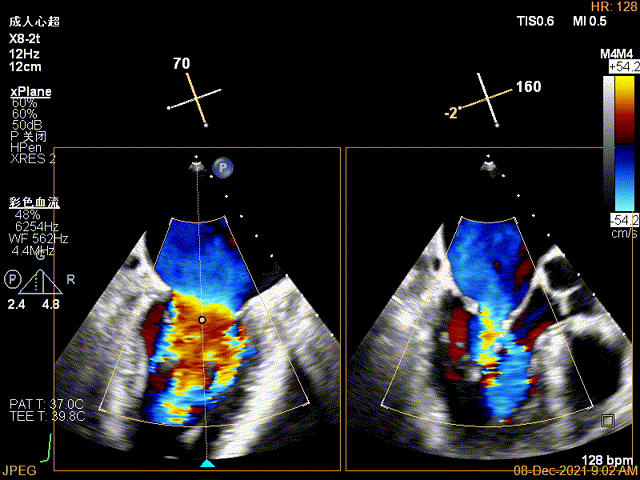

X-plane:下夹子尝试先捕获2区瓣叶

夹子关闭过程中,Color提示2区反流逐渐减少,残余反流位于夹子外侧

x-plane验证前后叶抓捕后bond明显